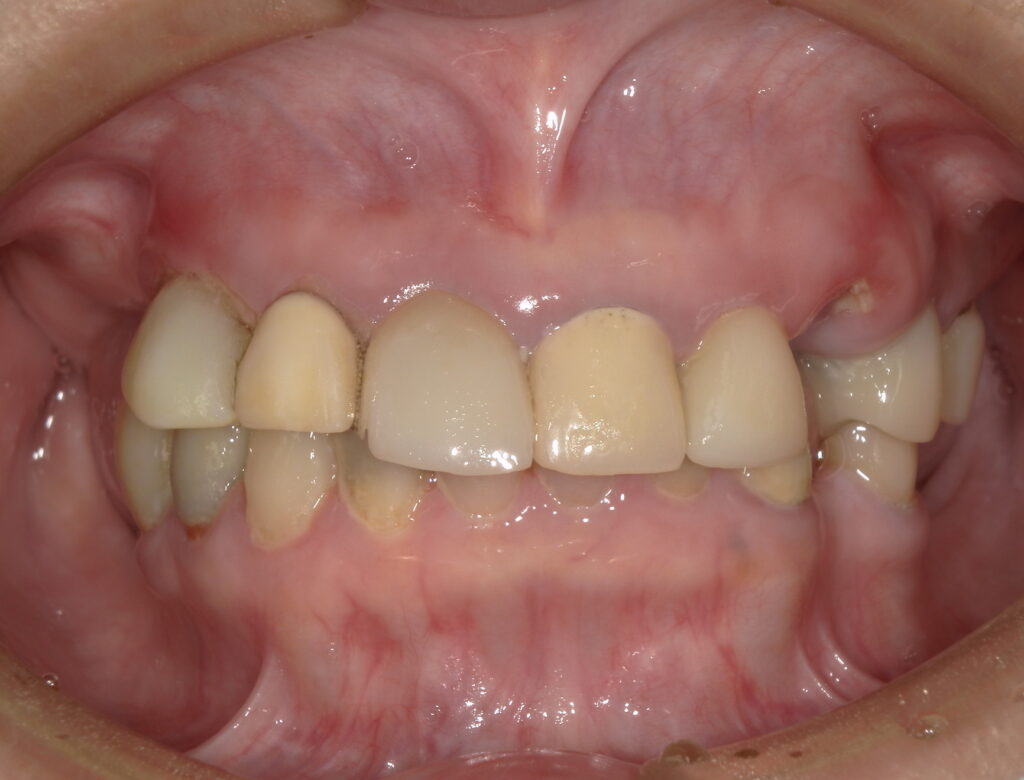

診査の結果、上顎は4本の歯を保存することが可能でした。

下顎は前歯9本を残すことができましたが、神経のない歯が多く、負担を分散する治療が必要な状態でした。